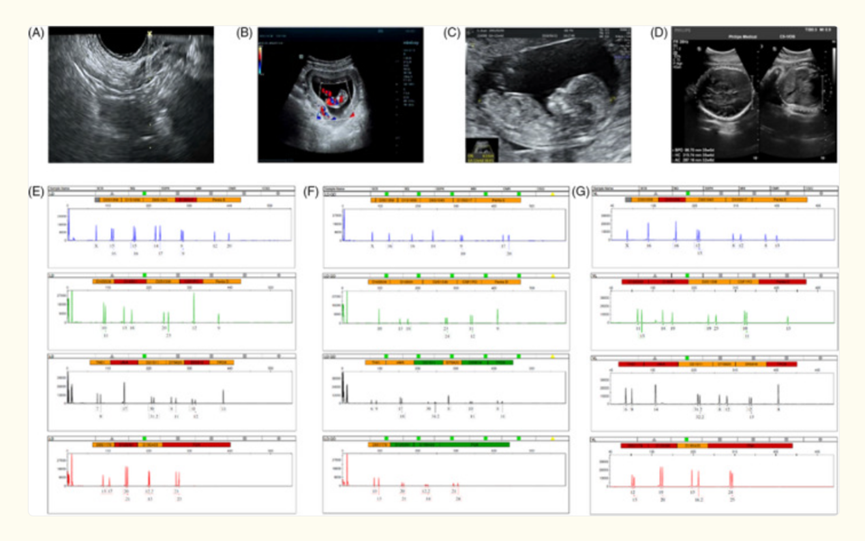

图片来自文献[5]

一项来自国内学者开展的研究中[5],研究人员选取了61 名符合条件的卵巢早衰患者,利用脐带间充质干细胞(UCMSCs)注射移植到患者的卵巢中,并分别进行了三次手术。结果显示,仅第一次手术后,就有超过 30%(31.1%)的患者的卵泡发育出现了明显的改善趋势,包括 AFC 上升、DFC 和 MFC 数量增加,以及 AMH 水平升高。生育方面,也有 15 名患者进行了取卵的操作,最后有 4 个宝宝顺利出生,而且都很健康。